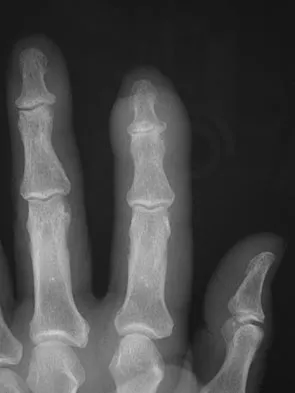

The condition shown in Figures 9a and 9b is most likely the result of

The clinical photograph and radiograph show gout, which is the result of urate deposition in the joint and soft tissues. Radiographs frequently reveal periarticular erosions. The crystals are intracellular and negatively birefringent under the polarized microscope. Treatment for acute flares include colchicines, indomethacin, and corticosteroids (including injections). Medications such as allopurinol help prevent recurrent flares. Tophi such as that seen in this patient are often confused with and associated with infection. Wortmann RL, Kelley WM: Crystal-induced inflammation: Gout and hyperuricemia, in Harris ED, Budd RC, Firestein GS, et al (eds): Kelley's Textbook of Rheumatology, ed 7. New York, NY, Elsevier Science, 2005, pp 1402-1429. Trumble TE (ed): Hand Surgery Update 3: Hand, Elbow, & Shoulder. Rosemont, IL, American Society for Surgery of the Hand, 2003, pp 433-457.